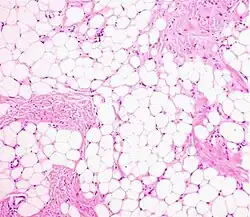

Histopathology of a lipoma: The mass is composed of lobules of mature white adipose tissue divided by fibrous septa containing thin-walled capillary-sized vessels.[25] H&E stain. -

Histopathology of the major differential diagnosis of a well-differentiated liposarcoma, lipoma-like subtype: It looks almost identical at low magnification, but a high magnification of a fibrous band shows spindle cells with enlarged, hyperchromatic nuclei. H&E stain. -